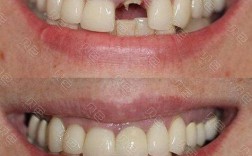

- 查看案例: 请医生展示类似病例的治疗前后照片,了解其技术水平。